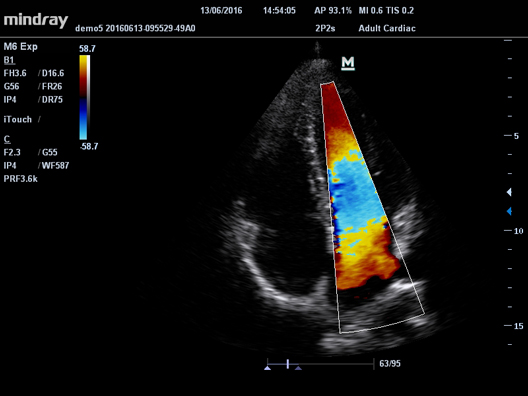

УЗ-сканер Mindray М6 exp представляет собой полнофункциональную портативную, размером с ноутбук, систему цветной допплерографии. Аппарат обеспечивает безупречную визуализацию в формате 2D. Оснащенная специализированными технологиями система М6 exp является оптимальным вариантом для применения.

HR Flow

Передовая технология на основе эксклюзивного алгоритма обработки изображений Mindray, обеспечивающая улучшенную визуализацию мельчайших сосудов и сложных структур потока.